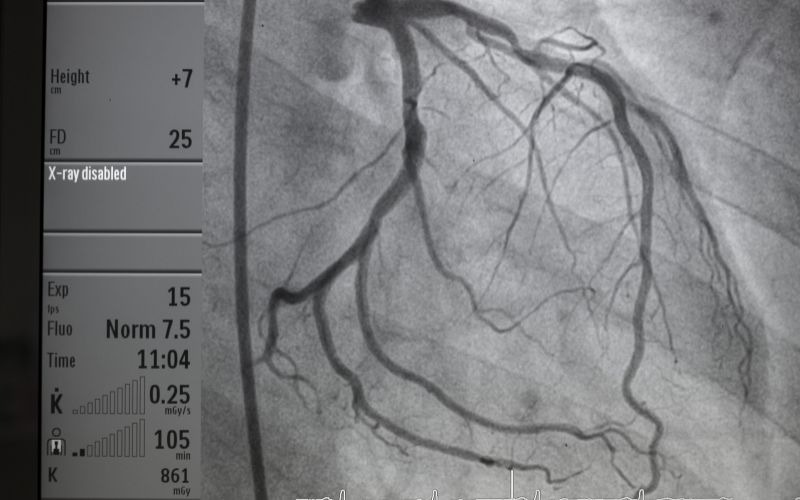

Koronarografia serca, znana również jako angiografia wieńcowa, to zaawansowana metoda diagnostyczna, uznawana za złoty standard w ocenie stanu tętnic wieńcowych.